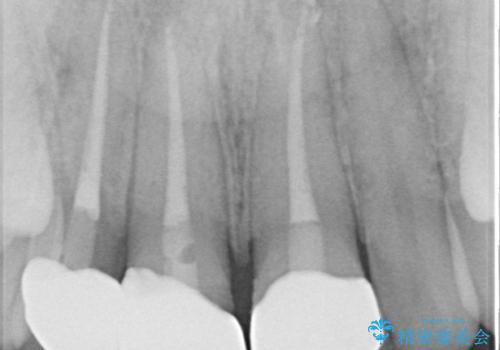

- 自転車で転んで前歯をぶつけたとのことで来院された患者様です。

事故後に受診した病院の歯科にて前歯2本の欠損した部分を修復されておりましたが、見た目が気になるとのことで、オールセラミッククラウンにて補綴治療を行うこととしました。

神経組織の状態を確認しましたが、片方は正常反応でしたが、他方は鈍い反応しかありませんでした。

速やかにオールセラミッククラウンにて補綴治療を行い、数ヶ月後に再度神経組織の状態を確認して、失活しているようであれば根管治療を行うこととしました。

しかしながら、補綴治療後間もなく再度自転車事故に遭い、追加1本の計3本を損傷する事態となりました。

再度損傷した3本は完全に失活した状態であったため、速やかに根管治療を行い、オールセラミッククラウンにて補綴治療を行うこととしました。

歯が欠けるほどの強い衝撃を受けると、歯根が溶けてしまう外部吸収という現象を起こすことがあるため、補綴治療後しばらく様子を見ておりましたが、何と三度自転車事故に遭いかけてしまいました。